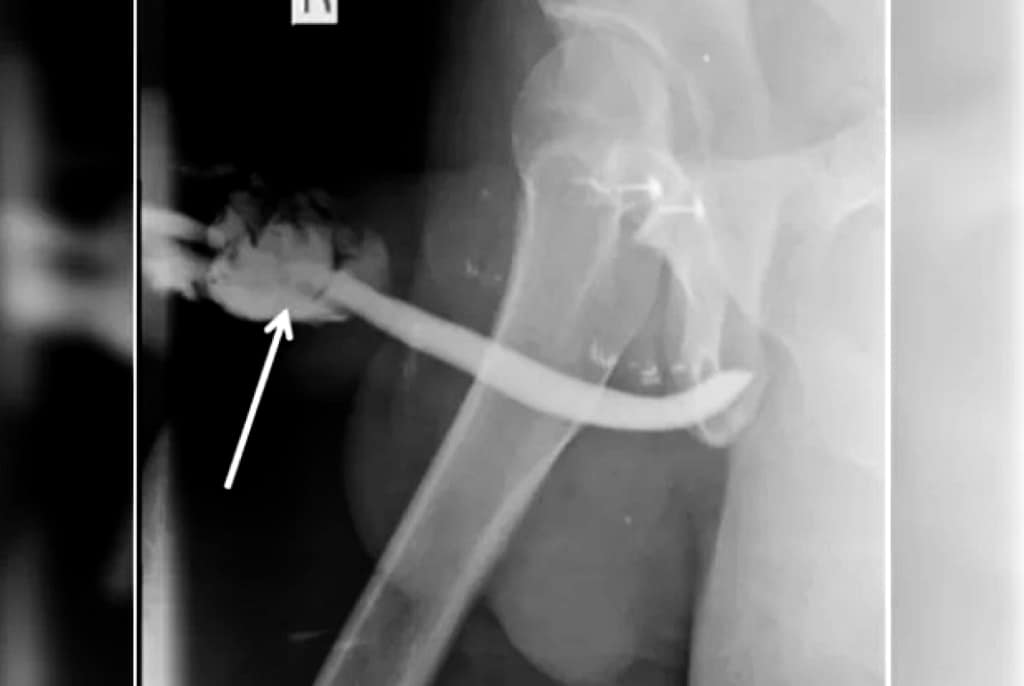

Radiografia mostrou rupturas em três pontos do meio do pênis, além de uma ruptura parcial de uretra com hematomas

O tanzaniano teve de passar por uma cirurgia de emergência no hospital de Kilimanjaro para que o órgão fosse reconstruído, já que o órgão torcido e em um formato que os médicos descreveram como semelhante a um balão. Depois do procedimento e do período de recuperação, o pênis do paciente voltou a funcionar normalmente.